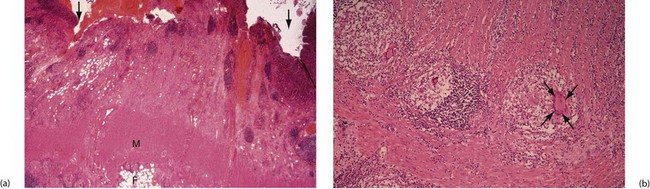

Fig. 28.6 Crohn's disease affecting the colon—histopathology

(a) Inflammation has produced fissure ulcers (arrowed) which extend into the muscle wall M. Lymphoid aggregates are also present and the inflammatory process extends into serosal fat F.

(b) High-power view showing well-formed granulomas with typical giant cells (arrowed), enabling a confident diagnosis of Crohn's disease to be made